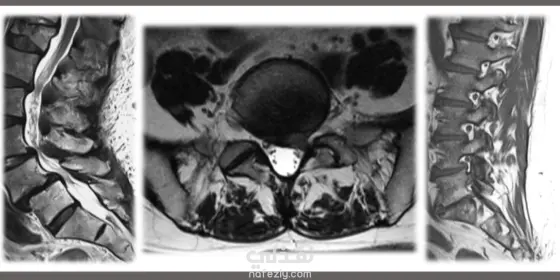

نموذج ذكاء اصطناعي لتحليل الرنين المغناطيسي للعمود الفقري القطني: يكتشف التغيرات التنكسية مبكرًا ويصنّف الحالات بدقة عالية. يحاكي أداء طبيب الأشعة من حيث التشخيص والرؤية الطبية. يولّد تقارير جاهزة للاستخدام السريري موثوقة وسريعة. يساهم في تحسين سرعة ودقة التشخيص بالمستشفيات ومراكز البحث، باستخدام أحدث تقنيات التعلم العميق